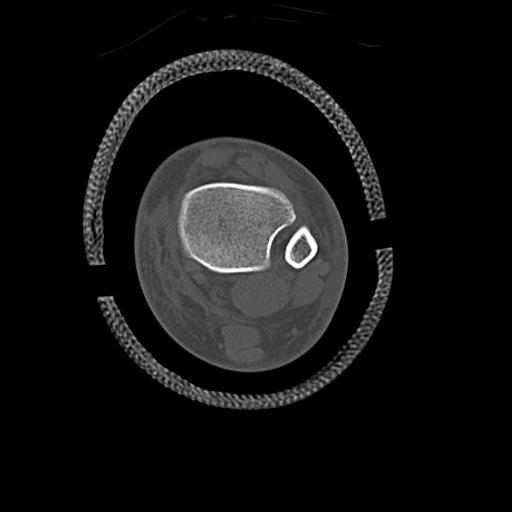

49554 3/13 膝 4R 3/16 4R 1/18 2R 78歳男性 膝蓋骨骨折